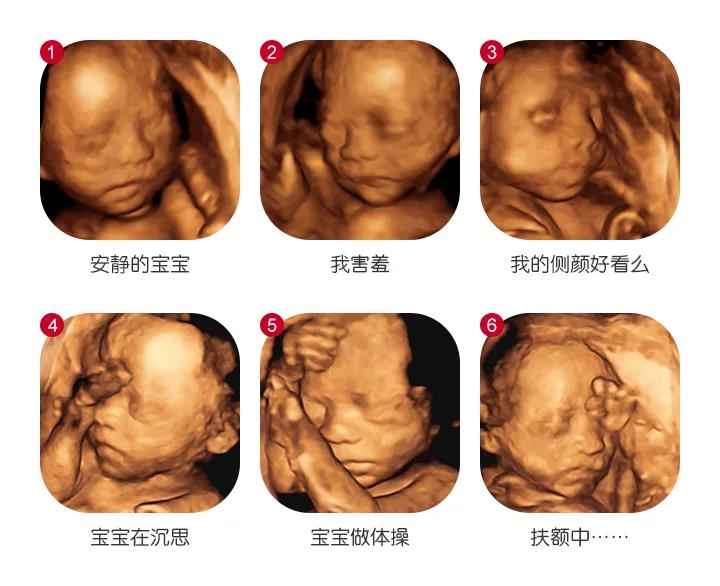

大连新百佳妇儿医院四维彩超费用是多少?四维彩超来院检查前要注意什么?大连新百佳妇儿医院李萍医生带您了解,大连新百佳妇儿医院引进先进的GE超声影像四维彩超仪器,多方位、多角度立体,显示胎儿生长发育情况,超越时空的”隔空对视“瞅瞅宝宝各种呆萌表情!

与宝宝的”超时空见面“